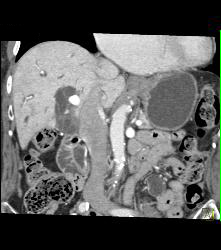

Atherosclerotic Disease Abdominal Aorta